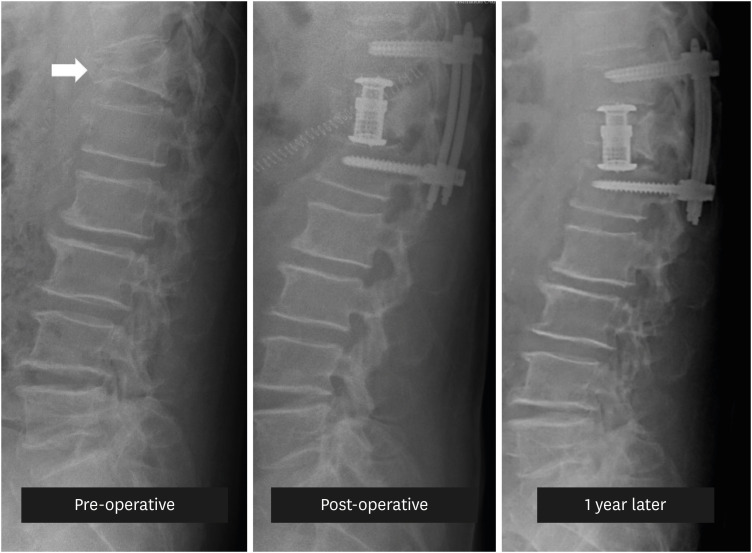

骨质疏松性椎体压缩骨折(OVCF)是导致老龄人口发病率和死亡率上升的重要原因。经年龄调整后,韩国是全球 OVCF 患病率最高的国家,男性每 10 万人中有 544 人,女性每 10 万人中有 1,575 人。此外,OVCF 患者发生其他骨折的风险更高,发生新的椎体骨折的风险最高可达 5 倍。因此,在治疗 OVCF 患者时,必须解决目前的症状,并采取预防措施防止进一步骨折。虽然药物治疗非常重要,但可能并不能满足所有 OVCF 患者的需求,更严重的患者通常需要物理治疗或手术干预。本综述旨在探讨针对 OVCF 患者的有效物理治疗方法,并总结针对患有各种基础疾病的高风险老年患者的手术技术。

Osteoporotic vertebral compression fractures (OVCF) significantly contribute to increased morbidity and mortality in aging populations. When adjusted for age, South Korea has the highest global prevalence of OVCF, with rates of 544 per 100,000 men and 1,575 per 100,000 women. Moreover, patients with OVCF are at a heightened risk of additional fractures, with the risk of new vertebral fractures being up to 5-fold higher. Therefore, in treating patients with OVCF, it is essential to address the current symptoms and take preventive measures against further fractures. Although pharmacological treatment is crucial, it may be insufficient for all patients with OVCF, with more severe cases often requiring physical therapy or surgical intervention. This review aimed to explore effective physical therapy methods for patients with OVCF and summarize surgical techniques for high-risk older patients with various underlying conditions.